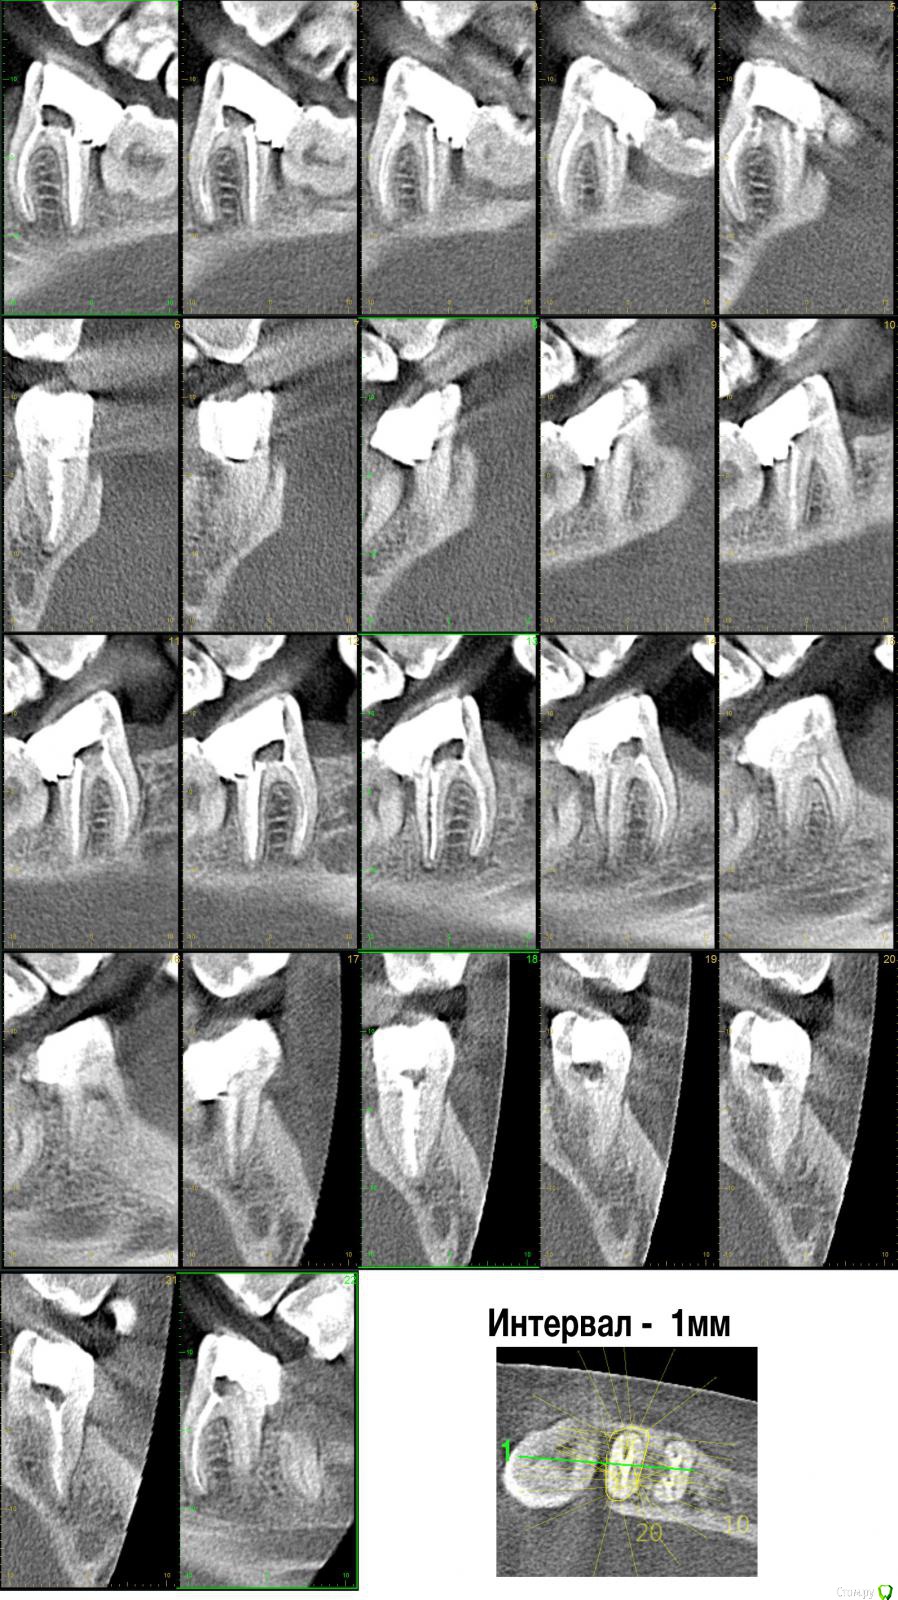

bestlion Опубликовано 21 мая, 2017 Автор Поделиться Опубликовано 21 мая, 2017 сделал круговые срезы на КТ (вдруг это как-то поможет) Ссылка на комментарий

krokomot Опубликовано 21 мая, 2017 Поделиться Опубликовано 21 мая, 2017 Уважаемый, вы очень поверхностно разбираетесь в стоматологии, чтобы брать на себя выбор конструкции. Посмотрев ваши срезы, больше стал склоняться к удалению вашего зуба. По поводу объяснения причин мы не проводим обучения и экскурсов в теоретическую стоматологию, читайте правиоа форума. Если вы и сами во всем разбираетесь никто вас тут переубеждать не станет. На ваш вопрос я уже ответил в первом сообшении, Скажу лишь, что в вашем случае нельщя сказать что 100% все идеально или все плохо. Скажу что качество пломбировки каналов приемлемо. Ссылка на комментарий